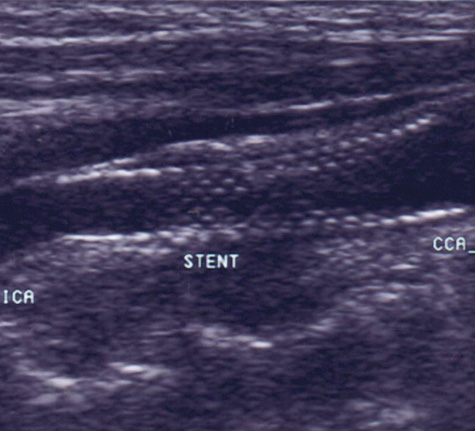

Fig. 2. This 48-year-old diabetic man suddenly developed confusion and clumsiness of the right hand. On examination, he had inability to identify objects by touch and difficulty identifying the right from the left. A. Fluid attenuated inversion recovery (FLAIR) MRI shows a left parietal cortical infarct. Two potential embolic sources were noted: a left ventricular apical clot was seen on echocardiography from a presumed recent silent myocardial infarction, and ultrasound and subsequent angiography confirmed a significant left internal carotid stenosis. B: A 70% left internal carotid artery origin stenosis is shown on angiography. Monitoring both middle cerebral arteries with transcranial Doppler showed microembolic signals only over the left, suggesting that the carotid atherostenotic plaque was active or destabilized. C: An interruption (arrow) of the normal Doppler flow pattern of the middle cerebral artery is shown, representing a microembolic signal. The artery was stented rather than revascularized by endarterectomy because of the recent myocardial infarction. D: A patent revascularized carotid is revealed by ultrasound; note the struts of the stent.

Carotid angioplasty and stenting is a novel endovascular approach to revascularizing the carotid artery. As a technique, it is in its infancy, and catheter technology and distal protection devices to prevent periprocedural strokes are constantly evolving. To date, no randomized study has shown superiority of this technique over surgical endarterectomy in the average patient,83,84 although direct comparisons between endarterectomy, and angioplasty and stenting are currently underway.85 However, high-risk patients appear to do better with endovascular approaches.86 In the author's opinion, for now angioplasty and stenting should be reserved for symptomatic patients who cannot undergo surgery or generalized anesthesia because of cardiac or pulmonary conditions. Certain situations, such as radiation-induced arteriopathy, contralateral occlusion or high-grade stenosis, or contralateral vocal cord paralysis, are relative contraindications to endarterectomy; in their presence angioplasty and stenting is an appropriate therapeutic choice. An example of carotid stenting is shown in Figure 2.